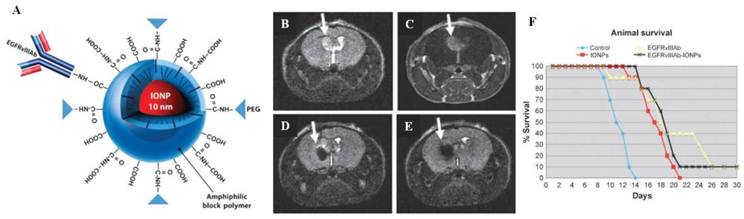

Hadjipanayis et al. employed an anti-epidermal growth factor receptor (EGFR) deletion mutant antibody to fabricate iron oxide nanoparticles for targeted imaging and therapeutic treatment of glioblastoma [52]. The EGFR variant III (EGFRvIII) deletion mutant is specifically expressed in malignant glioma cells but not in normal brain tissue. Selective binding to this mutant EGFR protein was achieved by creating a polyclonal rabbit antibody toward the chemically synthesized 14-amino-acid fusion junction sequence (EGFRvIIIAb). Covalent conjugation of the purified rabbit polyclonal EGFRvIIIAb to the amphiphilic triblock copolymer-coated iron oxide nanoparticles [53] yielded a stable glioblastoma-targeting theranostic agent (EGFRvIIIAb-IONPs) (Figure 1A). The EGFRvIIIAb-IONPs were effectively delivered to the intratumoral and peritumoral regions in the brain using convection enhanced delivery (CED), which is a continuous method of injection under a pressure gradient formed by the fluid containing the therapeutic agent [54]. Generally, CED prevents nanoparticles from becoming trapped in the liver, spleen, or circulating macrophages after intravenous administration, and it helps in bypassing the blood-brain barrier (BBB). CED is, therefore, increasingly used to distribute therapeutic agents for the treatment of malignant gliomas [55-57]. Athymic nude mice implanted with a human U87∆EGFRvIII glioma model tumor underwent CED of EGFRvIII-IONPs to test the accuracy of MRI monitoring and the efficacy of the antitumor effects. The T2-weighted MRI signal at the tumor site decreased after CED of EGFRvIII-IONPs, and the total area in which a signal drop was observed was larger 7 days after CED, showing that the nanoparticles had dispersed. A significant increase in survival was observed in animals that underwent CED with EGFRvIIIAb or EGFRvIIIAb-IONPs as a result of the inhibition of EGFR phosphorylation, whereas CED with the untreated control or IONPs did not result in an increase in the survival rate (Figures 1B-1F). These results indicated that the MRI-guided CED of EGFRvIIIAb-IONPs resulted in specific targeting of the devastating brain tumors.

Figure 1

(A) Schematic diagram showing EGFRvIII-IONPs. (B-F) Survival studies of nude mice implanted with the U87ΔEGFRvIII glioma model. (B) T2-weighted MRI showing a tumor region with a bright signal 7 days after tumor implantation (arrow). (C) A tumor is shown (arrow) after injection of a gadolinium contrast agent (Gd-DTPA). (D) The MRI signal decreased (arrow) after CED of EGFRvIIIAb-IONPs. (E) EGFRvIIIAb-IONP dispersion and T2 signal decrease (arrow) 4 days after CED. (F) Survival curve of the nude mice bearing U87ΔEGFRvIII cells after a treatment regimen of MRI-guided CED: the untreated control, IONPs, EGFRvIIIAb, or EGFRvIIIAb-IONPs. Reproduced with permission from ref. [52].